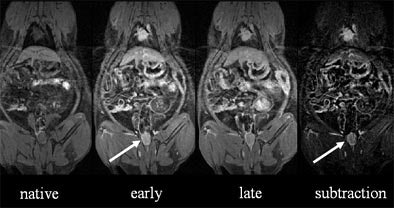

| (Left to right) The animal's chest and abdomen can be seen in the native unenhanced dataset, along with some motion artifact. Image quality improves slightly in early phase contrast, and significantly in late-phase contrast, four to five minutes after intravenous administration. Subtracting the native dataset from the early or arterial-phase dataset increases conspicuity of the colorectal lesion (arrow). All images courtesy of Dr. Christoph Herborn. |